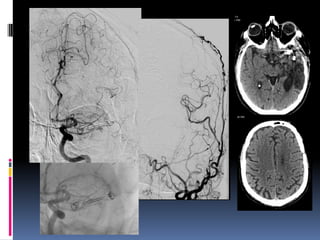

56 yr old, ischaemic stroke

56 yr old,ischaemic stroke